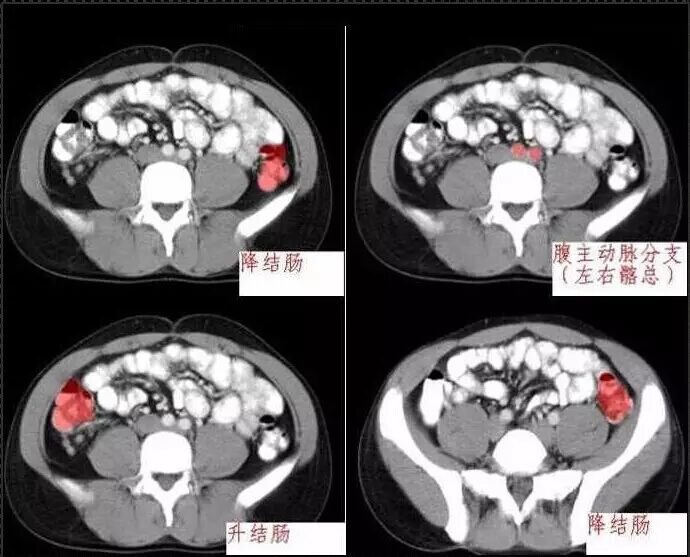

十分钟学会腹部CT解剖(多图)